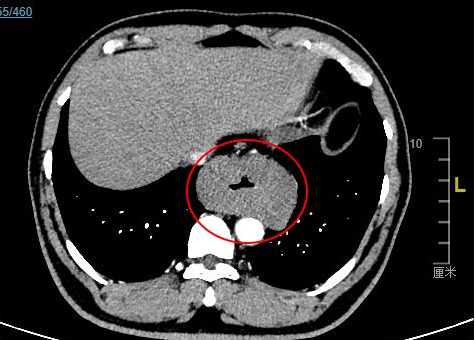

治疗前,杨浩贤主任医师为古先生安排了全面细致的术前检查。胸腹部CT检查结果提示,食管胸下段管壁不均匀环形增厚,最厚处达42mm,长约81mm,与胸主动脉相贴;超声胃镜检查确认了在距离门齿约35-40cm处,可见食管近全周粘膜下隆起肿物,表面粘膜光滑,起源于食管固有肌层,累及食管全周,病情非常复杂。

CT图像显示肿瘤环绕食管全周,压迫食管腔,肿瘤长径达8cm